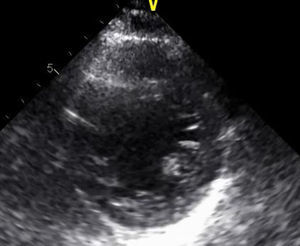

Monitorizada em ambiente de unidade de cuidados intensivos cardíacos, realizou ecocardiograma, que revelou ventrículo esquerdo de dimensões normais com fracção de ejecção do ventrículo esquerdo (FEVE) global ligeiramente deprimida (FEVE ± 45%) e imagens compatíveis com VENC a nível apical (trabeculações exuberantes com relação camada trabeculada/não trabeculada superior a dois e com fluxo detetado por Doppler de cor ao nível das mesmas) (Figuras 4 e 5). Foi efetuada coronariografia, revelando ausência de doença coronária.